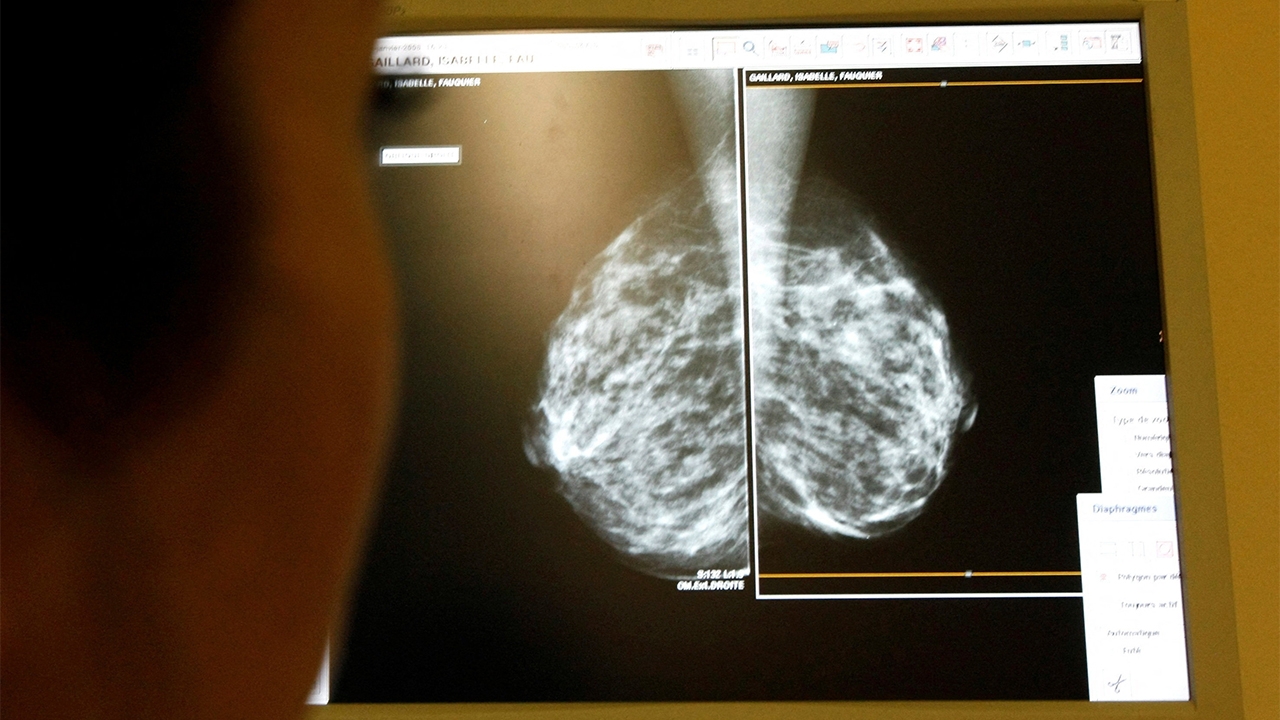

ปัจจุบันมะเร็งเต้านมเป็นมะเร็งชนิดที่พบบ่อยที่สุดในสหรัฐอเมริกา มีผู้ป่วยที่ได้รับการวินิจฉัยมากกว่า 240,000 รายทุกปี ข้อมูลล่าสุดของสถาบันโรคมะเร็งแห่งสหรัฐอเมริกา (American Cancer Society) เผยว่า สตรีผิวดำในสหรัฐฯมีอัตราการเป็นมะเร็งเต้านมก่อนอายุ 50 สูงกว่าอย่างมีนัยสำคัญ รวมถึงอัตราการเสียชีวิตด้วยมะเร็งเต้านมสูงกว่าผู้หญิงผิวขาวถึง 42%เมื่อเร็วๆนี้มีการศึกษาใหม่เกี่ยวกับการวิจัยการป้องกันมะเร็งของสมาคมโรคมะเร็งแห่งสหรัฐฯ เผยแพร่ในวารสาร Nature Genetics รายงานการวิจัยเพื่อระบุถึง “การกลายพันทางพันธุกรรม” ที่เชื่อมโยงกับมะเร็งเต้านม ซึ่งก่อนหน้านี้งานวิจัยหลายฉบับมุ่งเน้นไปที่สตรีที่มีเชื้อสายยุโรปเป็นหลัก แต่การวิจัยใหม่ขนาดใหญ่ครั้งนี้ มุ่งไปที่สตรีมากกว่า 40,000 รายที่มีเชื้อสายแอฟริกันในสหรัฐฯ สตรีชาวแอฟริกา และสตรีชาวบาร์เบโดส ในจำนวนนี้มี 18,034 คนที่ป่วยเป็นมะเร็งเต้านม การวิจัยเปิดเผยถึงยีนมะเร็งเต้านมใหม่ 12 ยีนที่พบในสตรีที่มีเชื้อสายแอฟริกัน ไม่รวมยีนมะเร็งเต้านม BRCA1 และ BRCA2 ที่เป็นที่รู้จักอยู่แล้ว การวิจัยชี้ว่ามียีนที่ผิดปกติ 6 ยีนสัมพันธ์กับความเสี่ยงที่เพิ่มขึ้นสำหรับมะเร็งเต้านมชนิด Triple-negative ซึ่งเป็นรูปแบบที่รุนแรงที่สุดของโรค และสตรีผิวดำมีความเสี่ยงเพิ่มขึ้นเกือบ 3 เท่าสำหรับมะเร็งเต้านมประเภทนี้เมื่อเทียบกับสตรีผิวขาวนักวิจัยเผยว่า การพบยีนมะเร็งเต้านมดังกล่าวอาจช่วยทำนายความเสี่ยงต่อโรคได้ดีขึ้น และเป็นหลักฐานในการส่งเสริมความเสมอภาคด้านสุขภาพ ในการให้คำปรึกษาและการทดสอบทางพันธุกรรม เพื่อช่วยระบุความเสี่ยงในการเกิดมะเร็งเต้านม.อ่าน “คอลัมน์หนังสือพิมพ์ไทยรัฐ” ทั้งหมดที่นี่